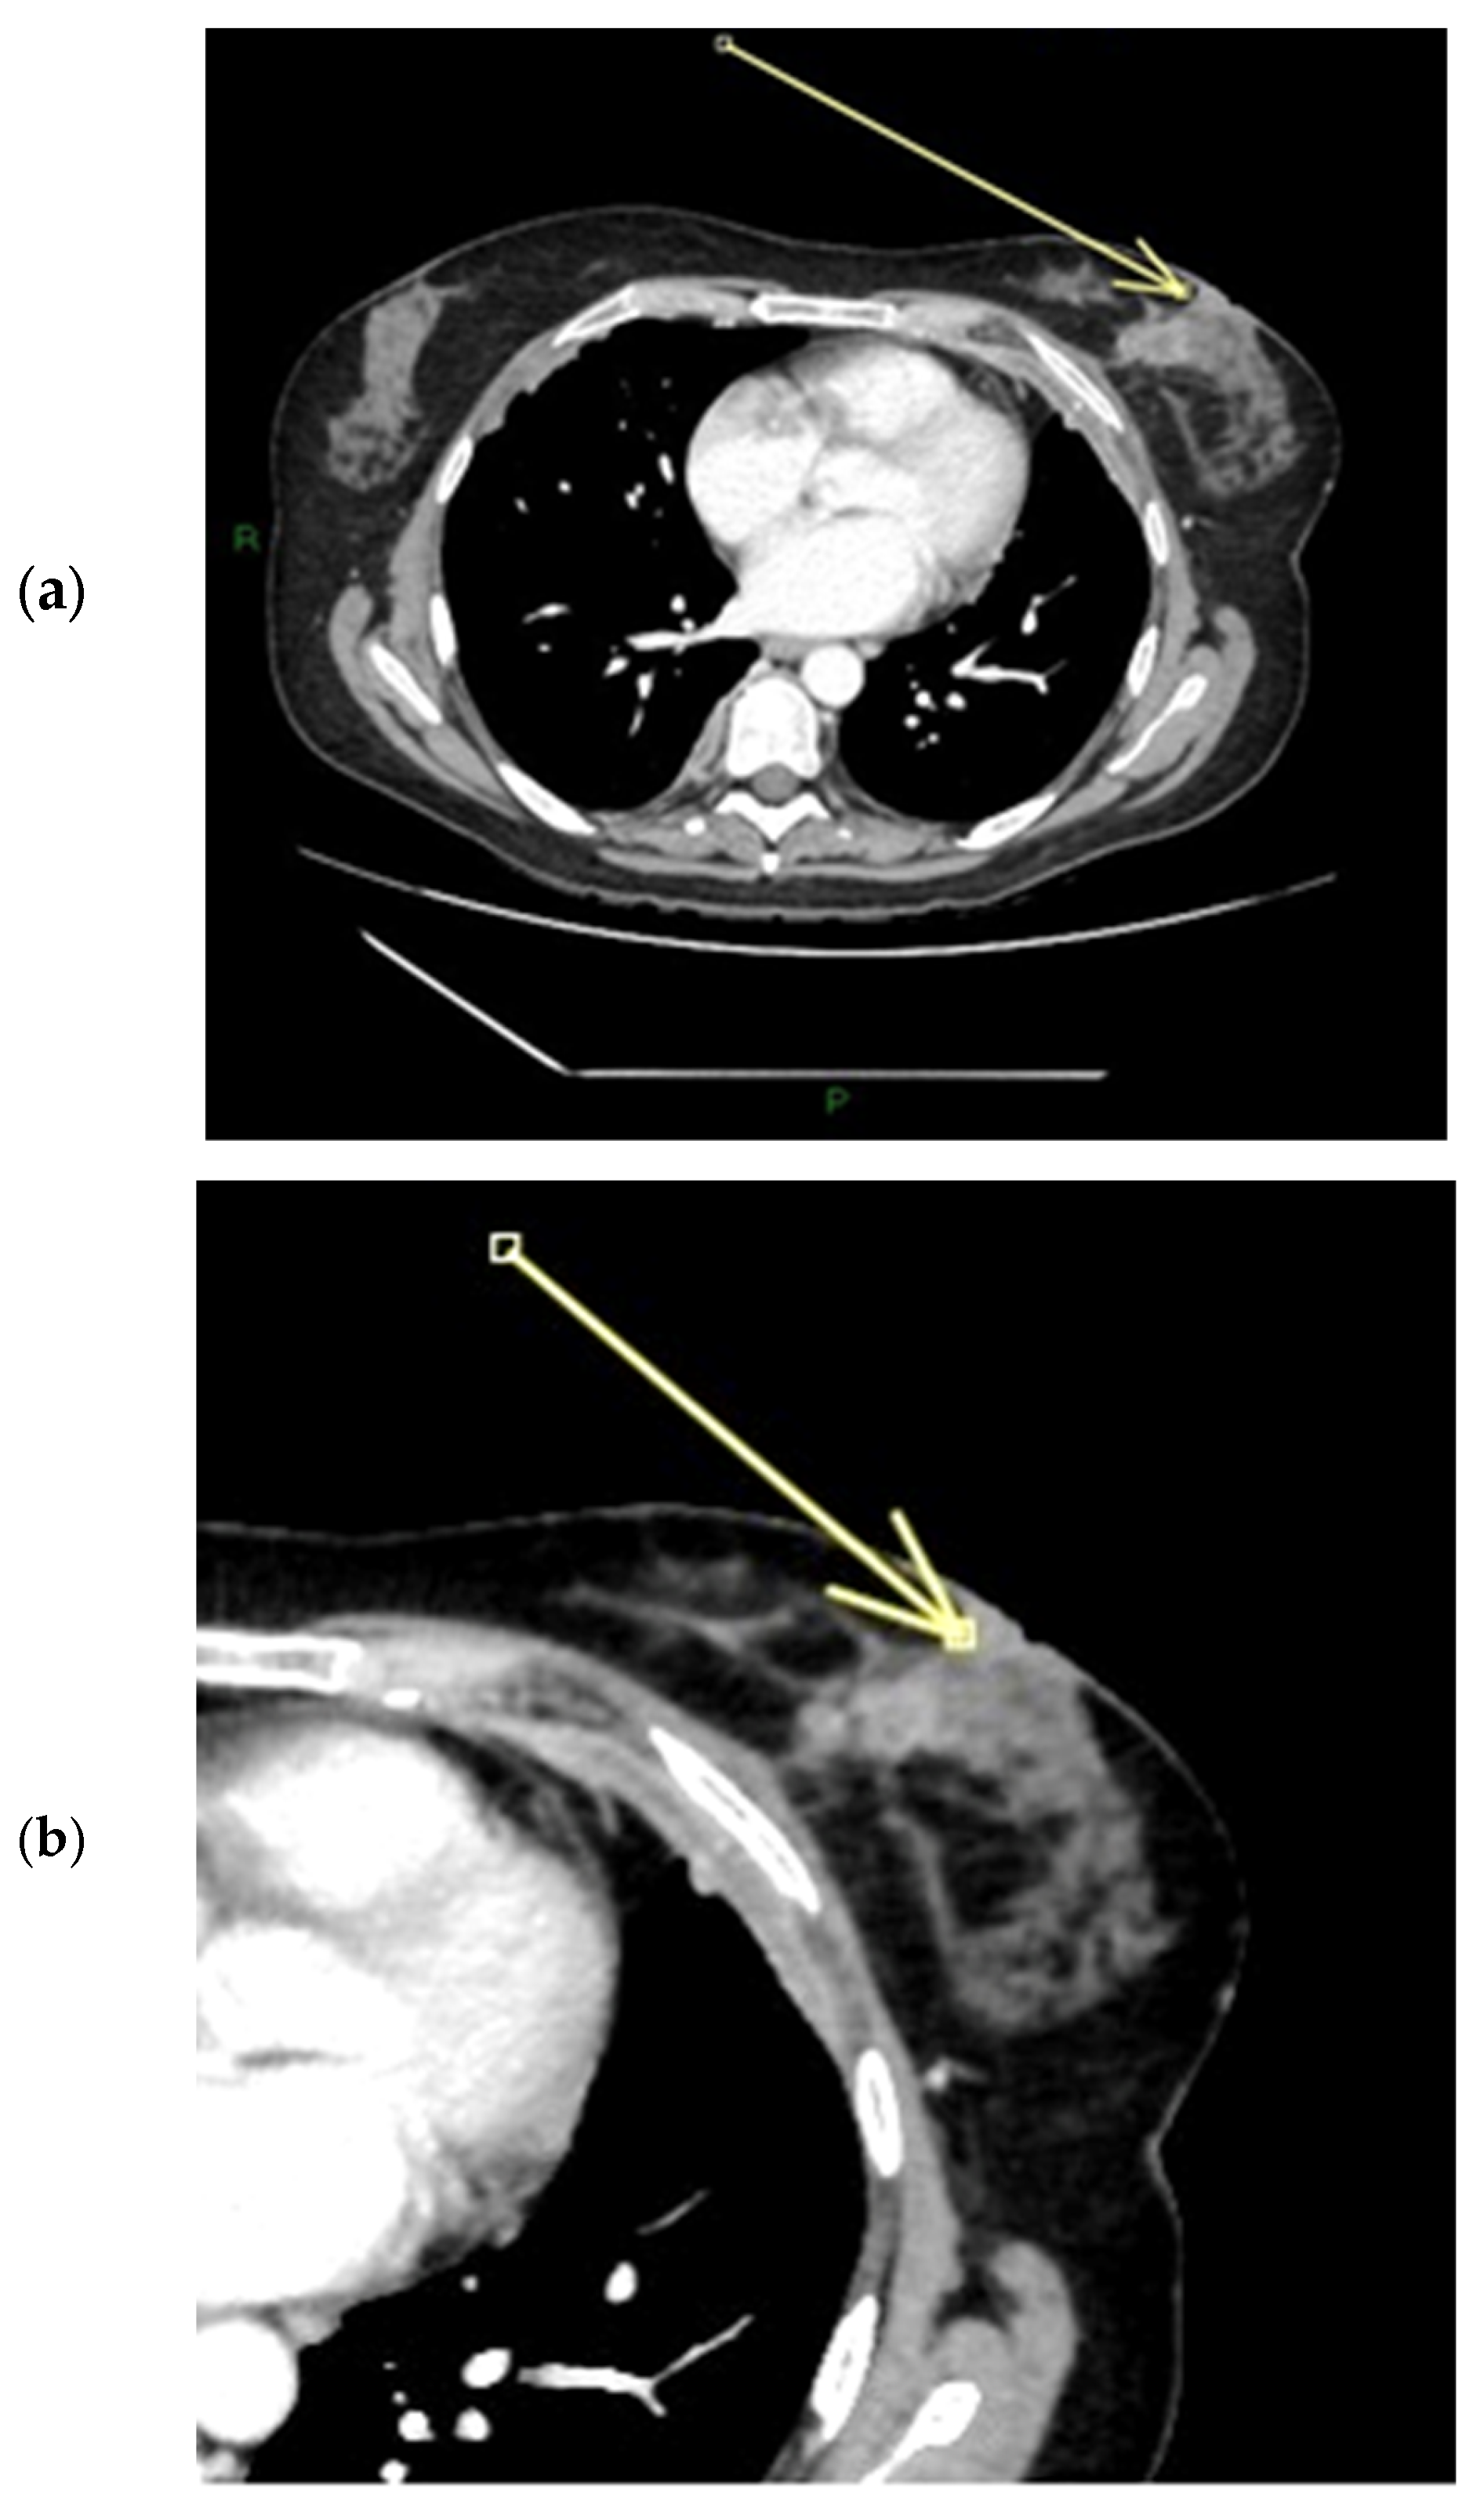

Figure 7.

(a–c) Patient’s name M.E. In the post-contrast fat-suppressed T1 sequences and in the MIP (maximum intensity projection) reconstruction of the first post-contrast fat-suppressed T1 sequence, we notice a gross area of pathological enhancement which affects the external quadrants of the left breast and infiltrates the nipple, without retraction (a,b). During ce-MR, SLE and NEZ enhancement patterns are present; the arrow indicates mild linear INE of the left breast nipple (c).

Figure 8.

(a,b) Patient’s name M.E. The ce-CT scan shows enhancement of the base of the left nipple alone (no body; arrow). Morphology of the nipple is everted.